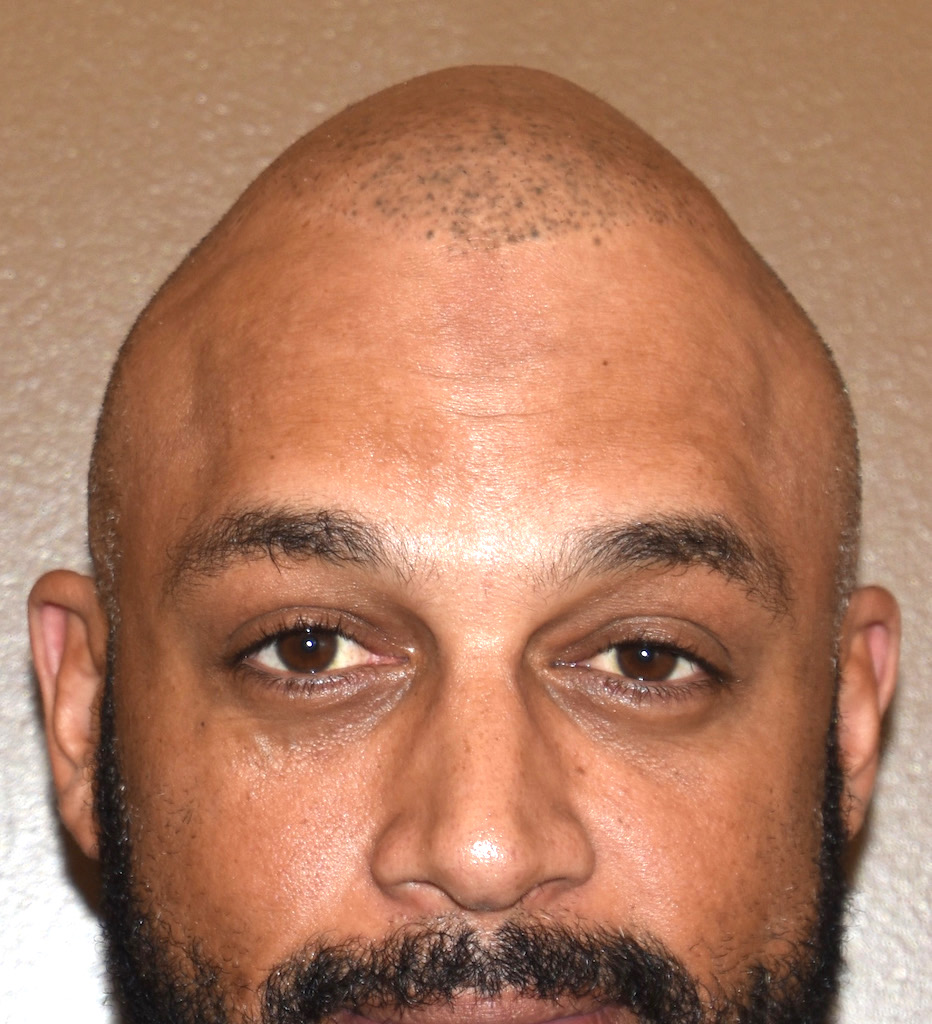

Patient 100

Desire for reshaping of an asymmetric flat back of the head in a shaved head male.

A combined back of the head reshaping procedure was done with a custom skull implant, sagittal ridge reduction and a right temporal muscle reduction.

Desire for reshaping of an asymmetric flat back of the head in a shaved head male.

A combined back of the head reshaping procedure was done with a custom skull implant, sagittal ridge reduction and a right temporal muscle reduction.